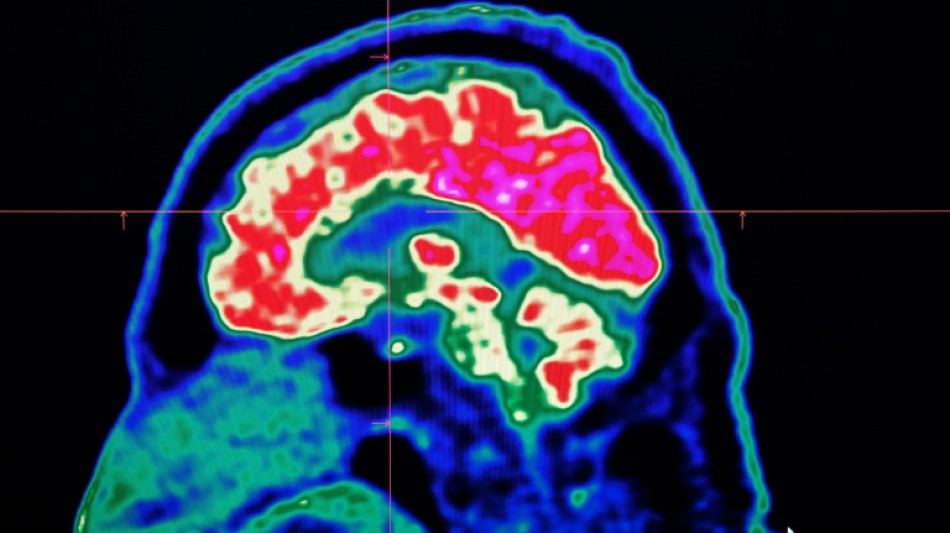

Final report casts doubt on existence of Canada mystery brain illness / Photo: Fred TANNEAU - AFP

A Canadian medical report published Friday found no evidence linking environmental factors to an unusual set of neurological symptoms affecting hundreds of people, a five-year saga that has shaken a small Atlantic province.

In 2021, health officials in New Brunswick launched an investigation involving 48 patients with a range of neurological symptoms but no apparent common illness. These included muscle spasms, memory loss, hallucinations and balance issues.

Some in the province of less than a million people began describing the condition as a mystery brain disease.

Provincial officials said at the time that the patient group could be suffering from a new disease not previously seen in Canada and began using the term "possible neurological syndrome of unknown cause."